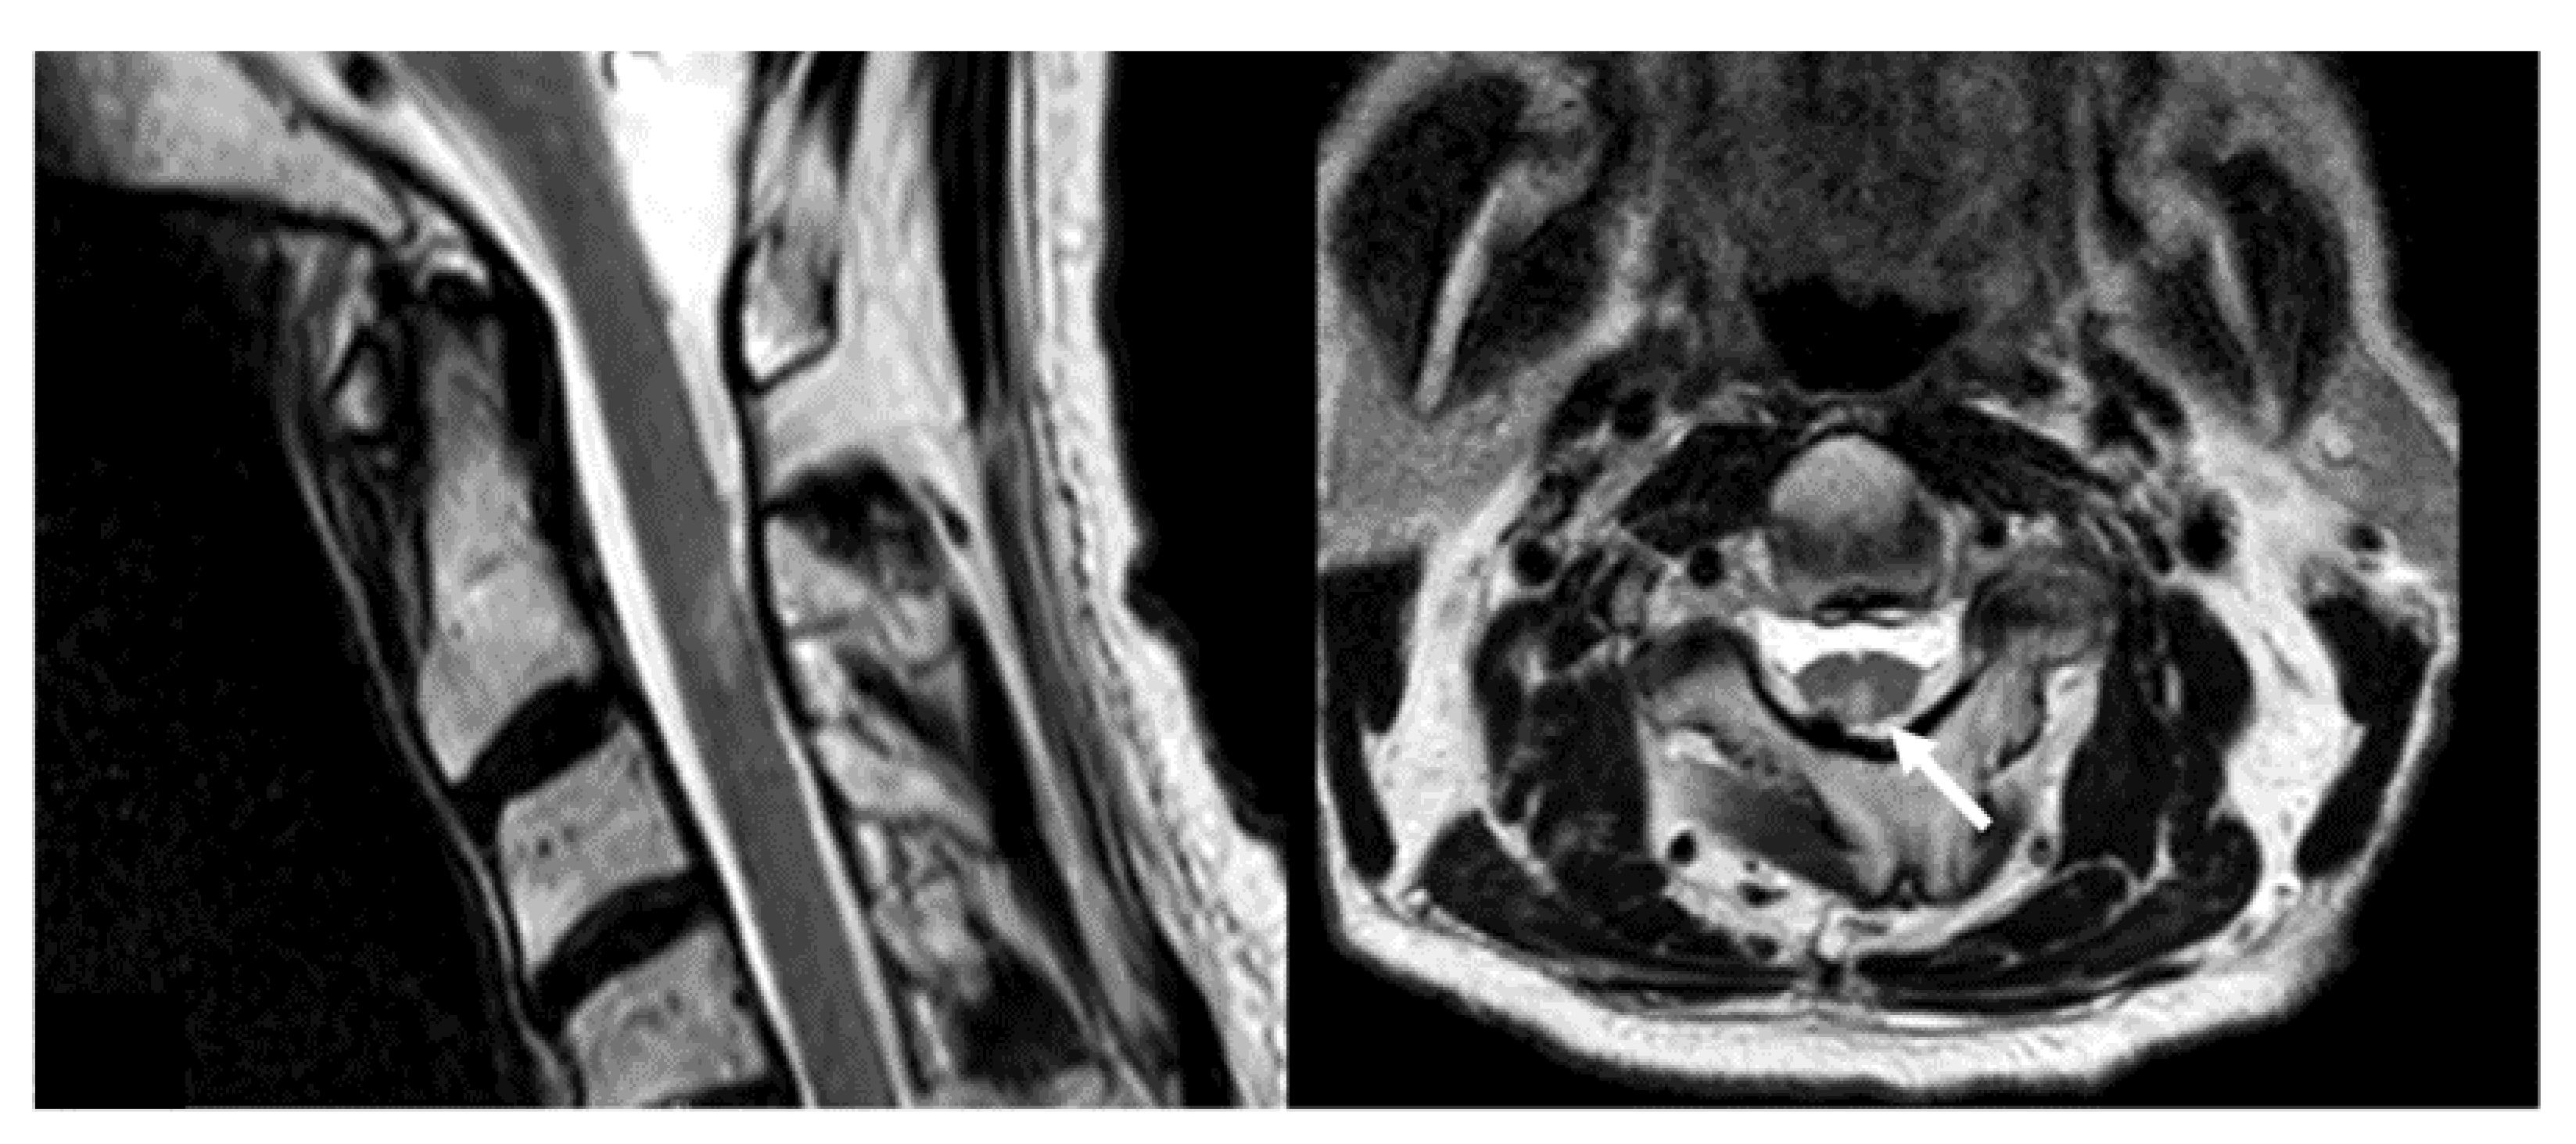

3.2. Safety and Complications